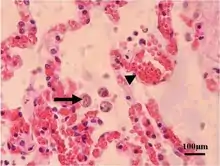

Acute toxoplasmosis is often asymptomatic in healthy adults.[13][14] However, symptoms may manifest and are often influenza-like: swollen lymph nodes, headaches, fever, and fatigue,[15] or muscle aches and pains that last for a month or more. It is rare for a human with a fully functioning immune system to develop severe symptoms following infection. People with weakened immune systems are likely to experience headache, confusion, poor coordination, seizures, lung problems that may resemble tuberculosis or Pneumocystis jirovecii pneumonia (a common opportunistic infection that occurs in people with AIDS), or chorioretinitis caused by severe inflammation of the retina (ocular toxoplasmosis).[15] Young children and immunocompromised people, such as those with HIV/AIDS, those taking certain types of chemotherapy, or those who have recently received an organ transplant, may develop severe toxoplasmosis. This can cause damage to the brain (encephalitis) or the eyes (necrotizing retinochoroiditis).[16] Infants infected via placental transmission may be born with either of these problems, or with nasal malformations, although these complications are rare in newborns. The toxoplasmic trophozoites causing acute toxoplasmosis are referred to as tachyzoites, and are typically found in various tissues and body fluids, but rarely in blood or cerebrospinal fluid.[17]

Due to the absence of obvious symptoms,[13][14] hosts easily become infected with T. gondii and develop toxoplasmosis without knowing it. Although mild, flu-like symptoms occasionally occur during the first few weeks following exposure, infection with T. gondii produces no readily observable symptoms in healthy human adults.[7][20] In most immunocompetent people, the infection enters a latent phase, during which only bradyzoites (in tissue cysts) are present;[21] these tissue cysts and even lesions can occur in the retinas, alveolar lining of the lungs (where an acute infection may mimic a Pneumocystis jirovecii infection), heart, skeletal muscle, and the central nervous system (CNS), including the brain.[22] Cysts form in the CNS (brain tissue) upon infection with T. gondii and persist for the lifetime of the host.[23] Most infants who are infected while in the womb have no symptoms at birth, but may develop symptoms later in life.[24]

In its lifecycle, T. gondii adopts several forms.[32] Tachyzoites are responsible for acute infection; they divide rapidly and spread through the tissues of the body. Tachyzoites are also known as "tachyzoic merozoites", a descriptive term that conveys more precisely the parasitological nature of this stage.[33] After proliferating, tachyzoites convert into bradyzoites, which are inside latent intracellular tissue cysts that form mainly in the muscles and brain. The formation of cysts is in part triggered by the pressure of the host immune system.[34] The bradyzoites (also called "bradyzoic merozoites") are not responsive to antibiotics. Bradyzoites, once formed, can remain in the tissues for the lifespan of the host. In a healthy host, if some bradyzoites convert back into active tachyzoites, the immune system will quickly destroy them. However, in immunocompromised individuals, or in fetuses, which lack a developed immune system, the tachyzoites can run rampant and cause significant neurological damage.[32]

Cats excrete the pathogen in their feces for a number of weeks after contracting the disease, generally by eating an infected intermediate host that could include mammals (like rodents) or birds. Oocyst shedding usually starts from the third day after ingestion of infected intermediate hosts, and may continue for weeks. The oocysts are not infective when excreted. After about a day, the oocyst undergoes a process called sporulation and becomes potentially pathogenic.[52] In addition to cats, birds and mammals including human beings are also intermediate hosts of the parasite and are involved in the transmission process. However the pathogenicity varies with the age and species involved in infection and the mode of transmission of T. gondii.[53]